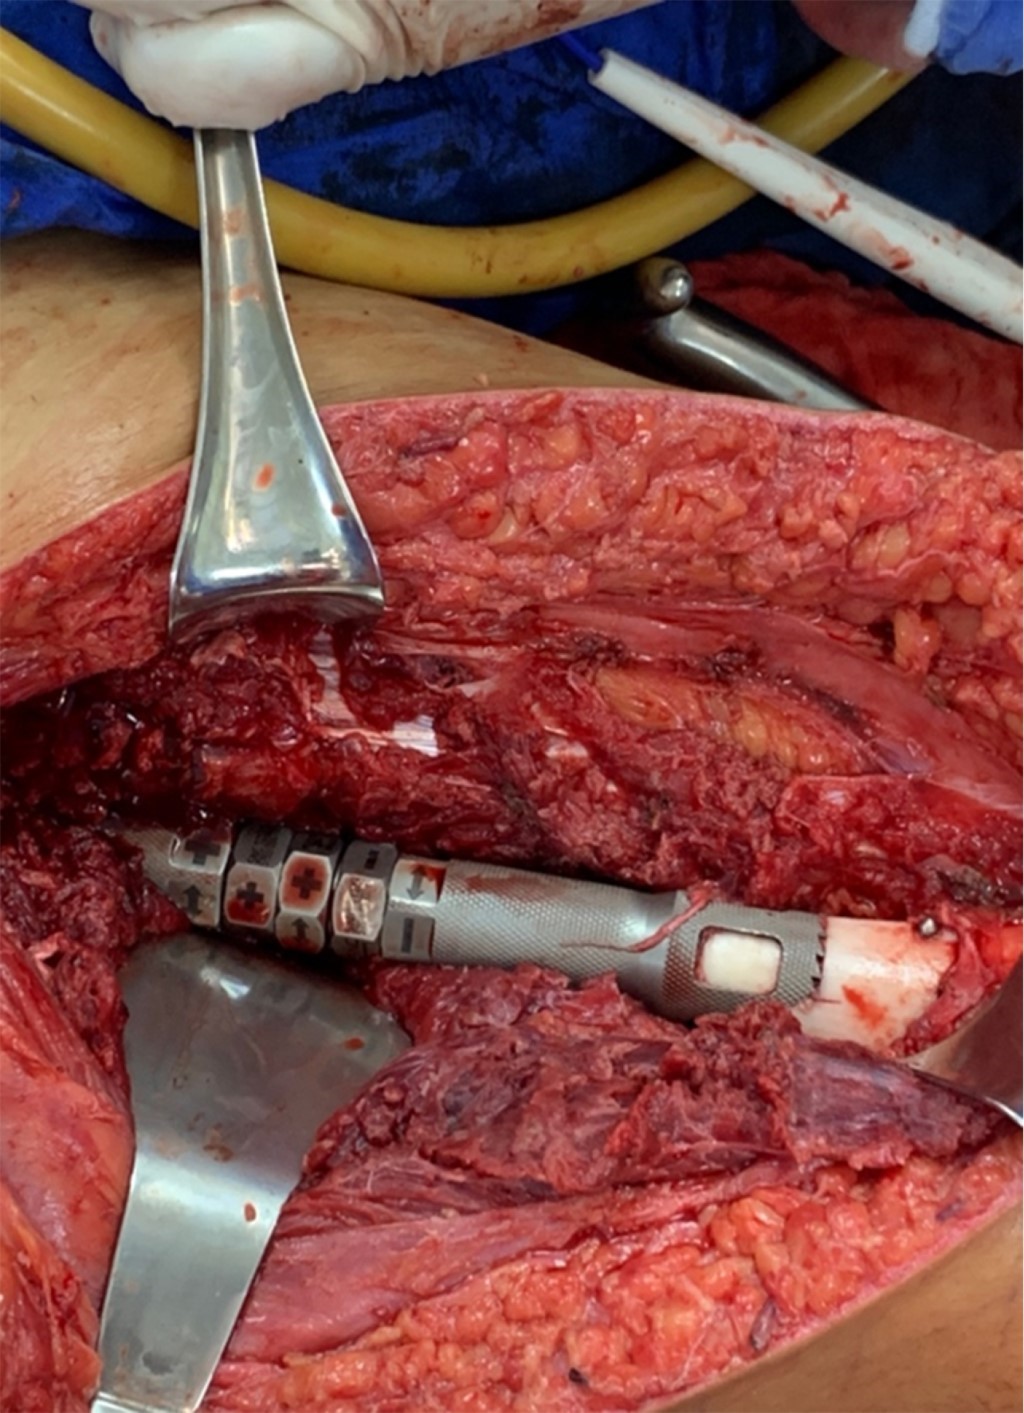

Con la paciente bajo anestesia general y en decúbito supino, se realiza asepsia, antisepsia y colocación de campos quirúrgicos estériles. Se opta por un abordaje anteromedial de fémur, mediante incisión longitudinal de aproximadamente 25 cm, disecando por planos hasta encontrar intervalo entre músculos recto femoral y vasto medial; después se encuentra el vasto intermedio, el cual se diseca hasta encontrar diáfisis femoral. Se observa tumoración en tercio medio de diáfisis femoral de aproximadamente 13 cm de longitud por 3 cm de ancho, el cual se reseca con bordes amplios, realizando osteotomía a 16 cm proximales de superficie articular de la rodilla (Figura 3); se envía muestra medular transquirúrgica, recibiendo confirmación de presencia de bordes libres por el Servicio de Patología. Se realiza segunda osteotomía a 16 cm distales del trocánter mayor, se envía segunda muestra de médula ósea, recibiendo reporte negativo para células malignas. Se realiza rimado de fémur proximal y distal con rimas diámetros 9, 10 y 10.5 hasta atravesar fosa digital proximalmente; se coloca asentador para hueso, regularizando el límite de la osteotomía. Se introduce clavo endomedular hasta limite distal establecido (Figuras 4 y 5) y se coloca prótesis diafisaria (Figura 6) con asentadores y coronas en extremos diafisarios, respectivamente. Se procede a colocar pernos de bloqueo, verificándose longitud de extremidad (Figura 7) comparando con la contralateral. Se repara intervalo entre recto femoral y vasto medial y se procede a cierre por planos.

Figura 3